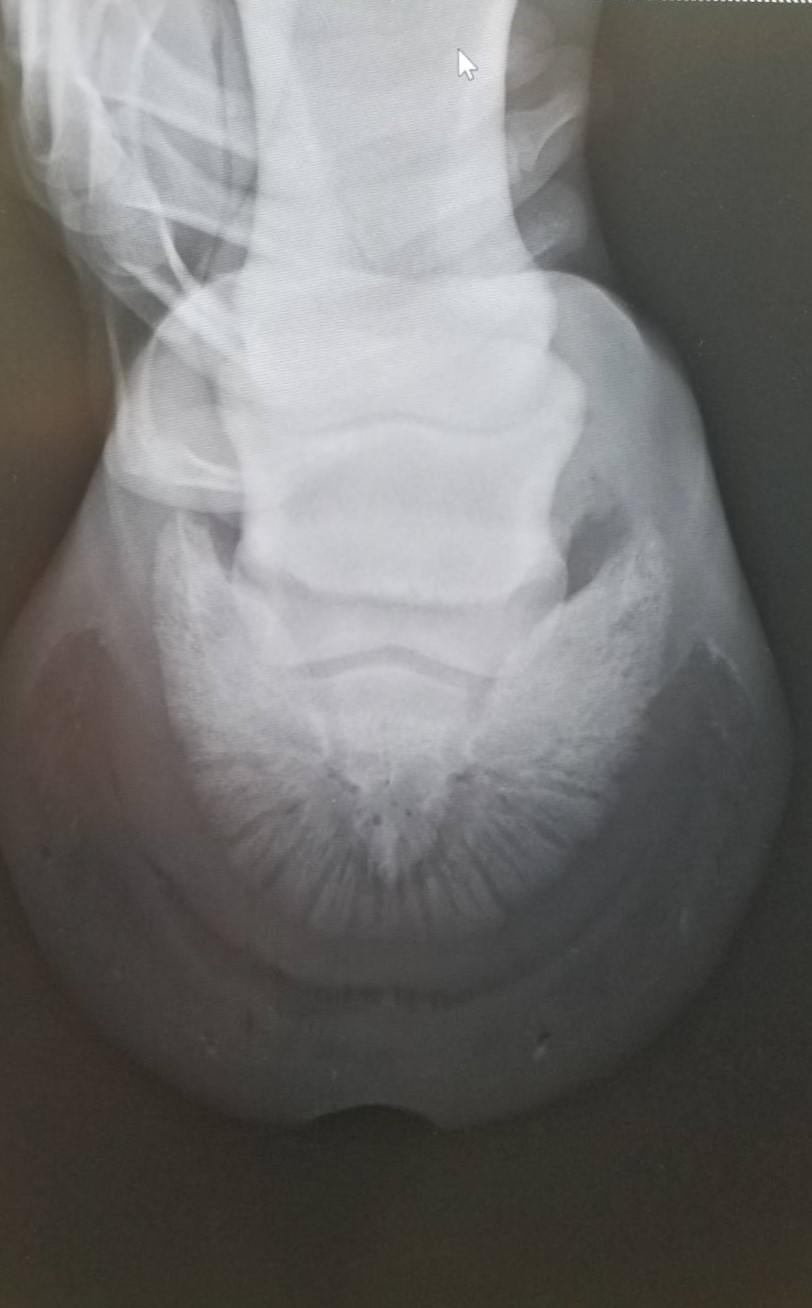

6月9日に左前脚を挫跖し、いったんは回復したものの、6月18日に再び左前の歩様が悪くなりました。調べたところ、蹄内にフレグモーネの症状が見られ、発熱し、白血球の数値も上がっていました。再度の挫跖か、蹄から菌が入ったものと考えられます。その後、熱と白血球の数値は落ち着きましたが、しばらくは左前脚を地面につけるのを嫌がるほど痛がっていました。6月28日のレントゲン検査の結果、中に溜まった膿が抜ける部分がなく、蹄骨の下を通って蹄球から抜けるという珍しい症例でした。そのため、膿が通り抜けた部分が空洞になって蹄底が上下に動く形になり、古い蹄の部分が当たり痛みが出ていたものと推測されます。

現在はACS(アドバンスクッションサポート)を蹄底に充填し、空洞を押さえつけるような形にしていることから、痛みはなく、歩様も正常です。今後は特に治療の必要はなく、蹄が伸びて、蹄の中の状態が改善されるのを待つだけという状況です。獣医師、装蹄師の診断では、蹄鉄を履かせて乗り出すまでに至るには1ヶ月程度必要とのことです。